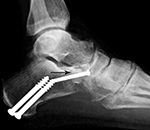

46 year-old man with posterior tibial tendon tear, Achilles tendon contracture, and planovalgus foot alignment. He was treated with Achilles tendon reattachment and two large partially threaded cancellous bone screws stabilizing a mid-calcaneal osteotomy. In the anterior portion of the calcaneus there is an autogenous iliac crest bone plug (arrow) stabilized by a fully threaded cortical bone screw.